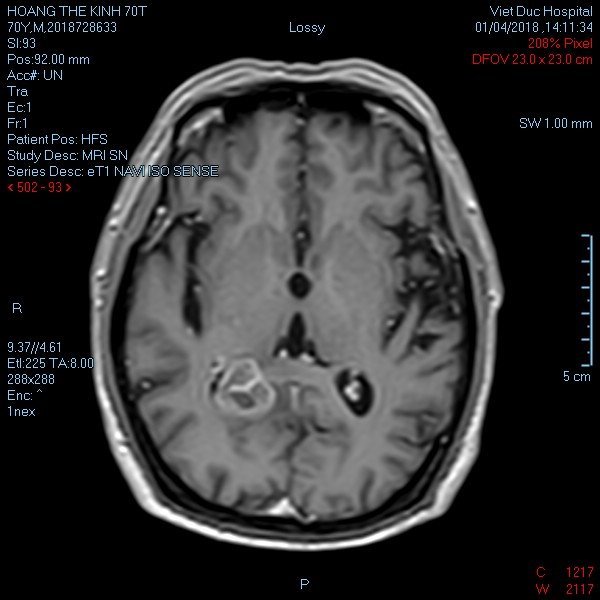

U não à? Em nghĩ Mợ nên kiểm tra và chụp chiếu tại một BV độc lập khác ạ, Đã gọi là chuẩn đoán mà mợ, Đôi khi nó cũng có sai số đó ạ :)

Cảm ơn lời chúc của mợ. Bố em tuổi cao mà khối u nằm rất sâu đây, nhưng phương tiện và chuyên môn của bác sĩ giờ tốt rồi mợ ạ

Xin chia sẻ cùng mợ, vì bố đẻ em cũng đang điều trị u thần kinh đệm.

Gần giống với cụ ông nhà mình. Cũng là u thần kinh, nhưng nó là u vỏ giây thần kinh ngoại biên ụ ngồi bên phải, kiên cường lắm nhưng giờ cụ cũng yếu lắm rồi, như ngọn nến trước gió vậy. Đồng hương xin chia sẻ với cụ và mợ thớt.

Mợ đưa cụ đi khám lại nhé, và cố liên hệ 1 bác sỹ phẫu thuật tốt vào. Người nhà em thì ngày xưa là giáo viên, được học trò quý nên học trò lo cho cả. Phẫu thuật cho ng nhà em là bác sỹ phẫu thuật giỏi tay nghề nhất VN thời kỳ đó.

Các bác sỹ VN giỏi lắm mợ à. Cơ bản là mình cần ổn định tâm lý cho người thân, và chăm sóc trước và sau phẫu thuật thật tốt và khoa học.

Chào mợ, mợ có thể nói rõ hơn về bệnh u não của mợ không. Bố đẻ mình năm 2008 cũng bị u màng não, nhưng tệ nhất là nó bao vào động mạch cảnh. mọi thứ coi như bế tắc hoàn toàn bv trả về. một mắt bố mình bi lồi ra vì cái u to bằng quả trứng gà, nhưng vì kiên trì và quyết tâm lang thang, lê la nhờ vả cac bệnh viện. sau có 3 phương án mổ mở, 1 sing: 2 việt pháp: 3: Việt đức, sau chốt VĐ vì hai lý do, bs việt nam mổ thần kinh ngang ngửa sing. troang trường hợp xấu nhất đứt động mạnh cảnh tì e kíp cấp kiu cảu viẹt đức đủ sức cầm máu: đi sinh thì cũng không hơn về tay nghề. còn việt pháp cũng nhận mổ nưng bên đó không có e kíp cấp kíu trong trường hợp đứt động mạch. Chốt mổ Việt Đức. sau đó hơn một năm mổ lần thứ 2 bằng giao GAMMA tại trung tâm ung bướu và trị xạ BV bạch mai lần này không mổ mở (bon tự tìm hiểu về gamma) lần một- lần thứ ba cũng vẫn mổ giao Gamma tại đó. và giờ 5 năm rồi bố mình không đi khám lại nữa mặc dù họ vẫn khuyến cáo nên đi khám định kỳ lại, nhưng giờ bố mình ngại đi lại nên ko đi